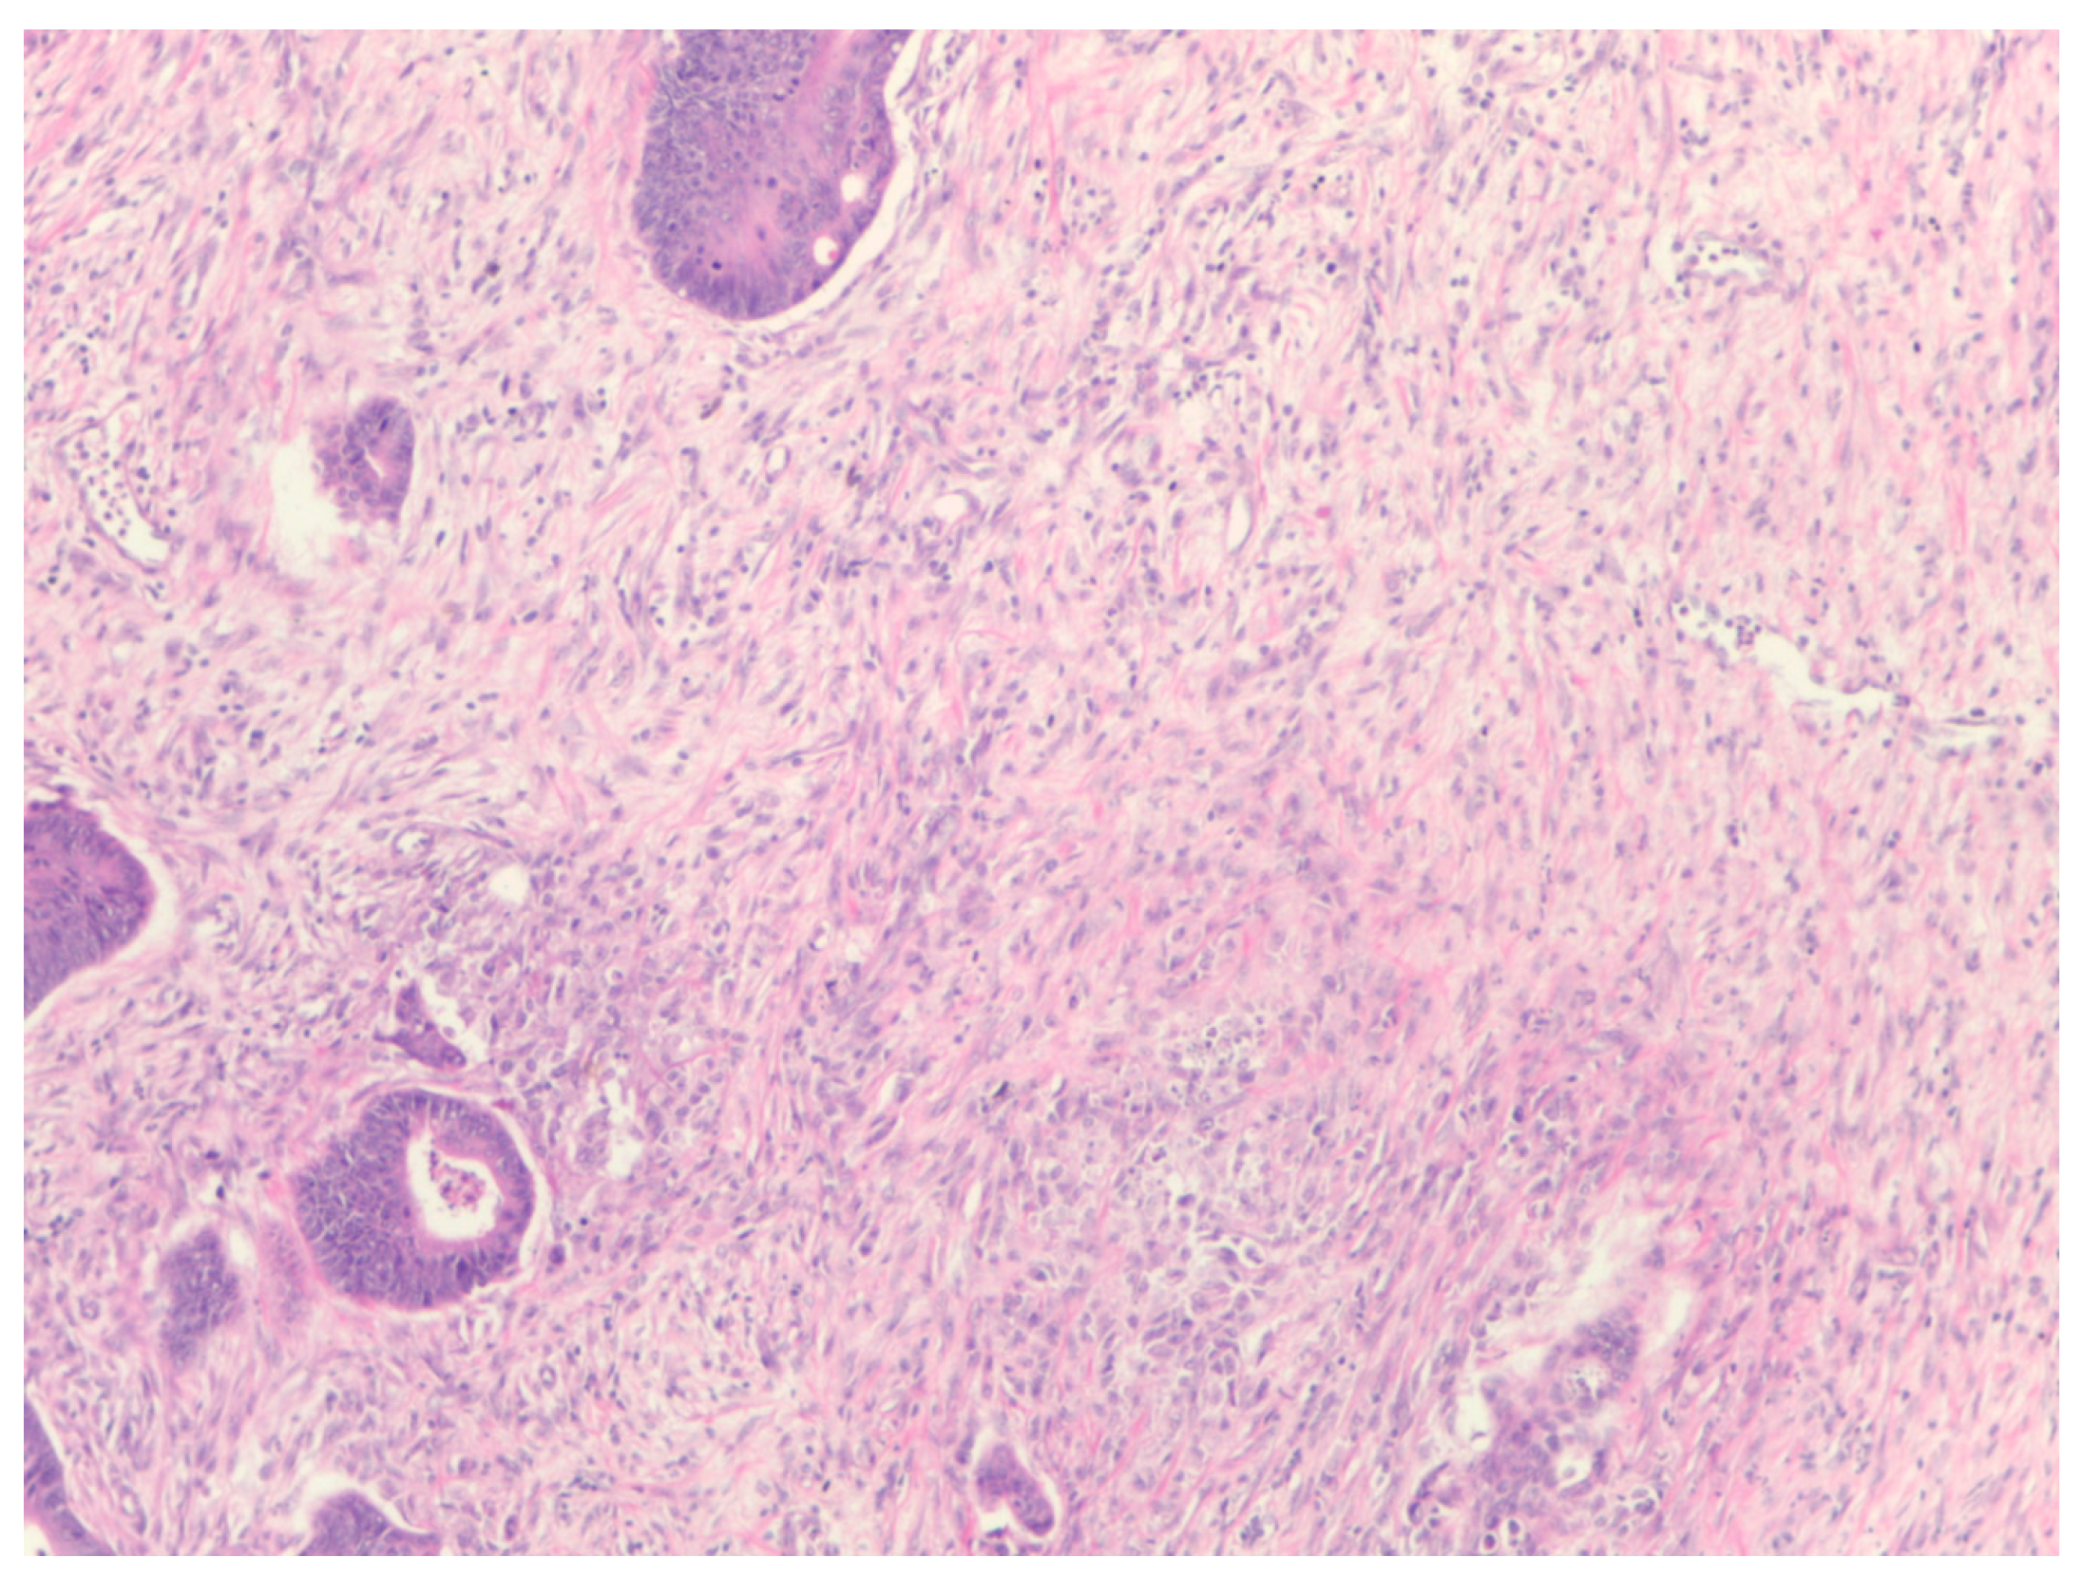

Unselective Measurement of Tumor-to-Stroma Proportion in Colon Cancer at the Invasion Front—An Elusive Prognostic Factor: Original Patient Data and Review of the Literature

2. Materials and Methods